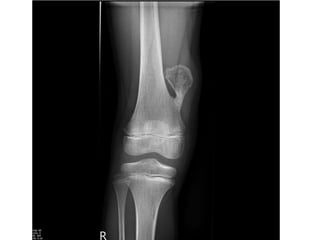

• The lesion classically presents radiographically as

intracortical osteolysis, most commonly affecting the

anterior cortex of the tibia (Figure 9.23).

• There is expansion of the cortex to accommodate the lesion

which typically has a soap bubble appearance.

• There is a narrow zone of transition between the lesion and

normal bone with a surrounding rim of sclerotic bone on

the medullary side, which may obscure the medullary

canal.

• MRI demonstrates a cortical lesion with a surrounding area

of sclerosis which demarcate the lesion from its

comparable malignant variant, adamantinoma, which

typically demonstrates a ‘moth-eaten’ margin with

medullary involvement.

OSTEOFIBROUS DYSPLASIA • Osteofibrousdysplasia (OFD) is a benign, non-osseous lesion of bone typically seen in the anterior cortex of the tibia, particularly in children or teenagers. • It is commonly seen in children in the first decade and can on rare occasions be polyostotic. • It is almost exclusively seen in the tibia but can on rare occasion affect the ipsilateral fibula or be bilateral at presentation. • It presents with moderate expansion of bone which is manifest as a palpable lump or progressive bowing of the tibia. • It is usually painless but stress fractures and pathological fractures can occur.

• 34.

• The lesionclassically presents radiographically as intracortical osteolysis, most commonly affecting the anterior cortex of the tibia (Figure 9.23). • There is expansion of the cortex to accommodate the lesion which typically has a soap bubble appearance. • There is a narrow zone of transition between the lesion and normal bone with a surrounding rim of sclerotic bone on the medullary side, which may obscure the medullary canal. • MRI demonstrates a cortical lesion with a surrounding area of sclerosis which demarcate the lesion from its comparable malignant variant, adamantinoma, which typically demonstrates a ‘moth-eaten’ margin with medullary involvement. • Histologically, osteofibrous dysplasia appears as irregular fragments of woven bone rimmed by layers of lamellar bone laid down by osteoblasts.

• 35.

• The fibrouscomponent consists of bland spindle cells with collagen production and a matrix that may be myxoid or fibrous. • The histological appearance can be differentiated from fibrous dysplasia by the absence of keratin-positive epithelial cells in OFD, and from adamantinoma by the absence of epithelial cell clusters. • These three comparable lesions behave very differently in their natural history, however: OFD tends to progress through the first decade of life, stabilizing during the second and often healing or resolving spontaneously thereafter. • Treatment, therefore, is rarely indicated except in exceptional circumstances of severe progressive deformity. • if ever, results in metastases, which differentiates it from adamantinoma